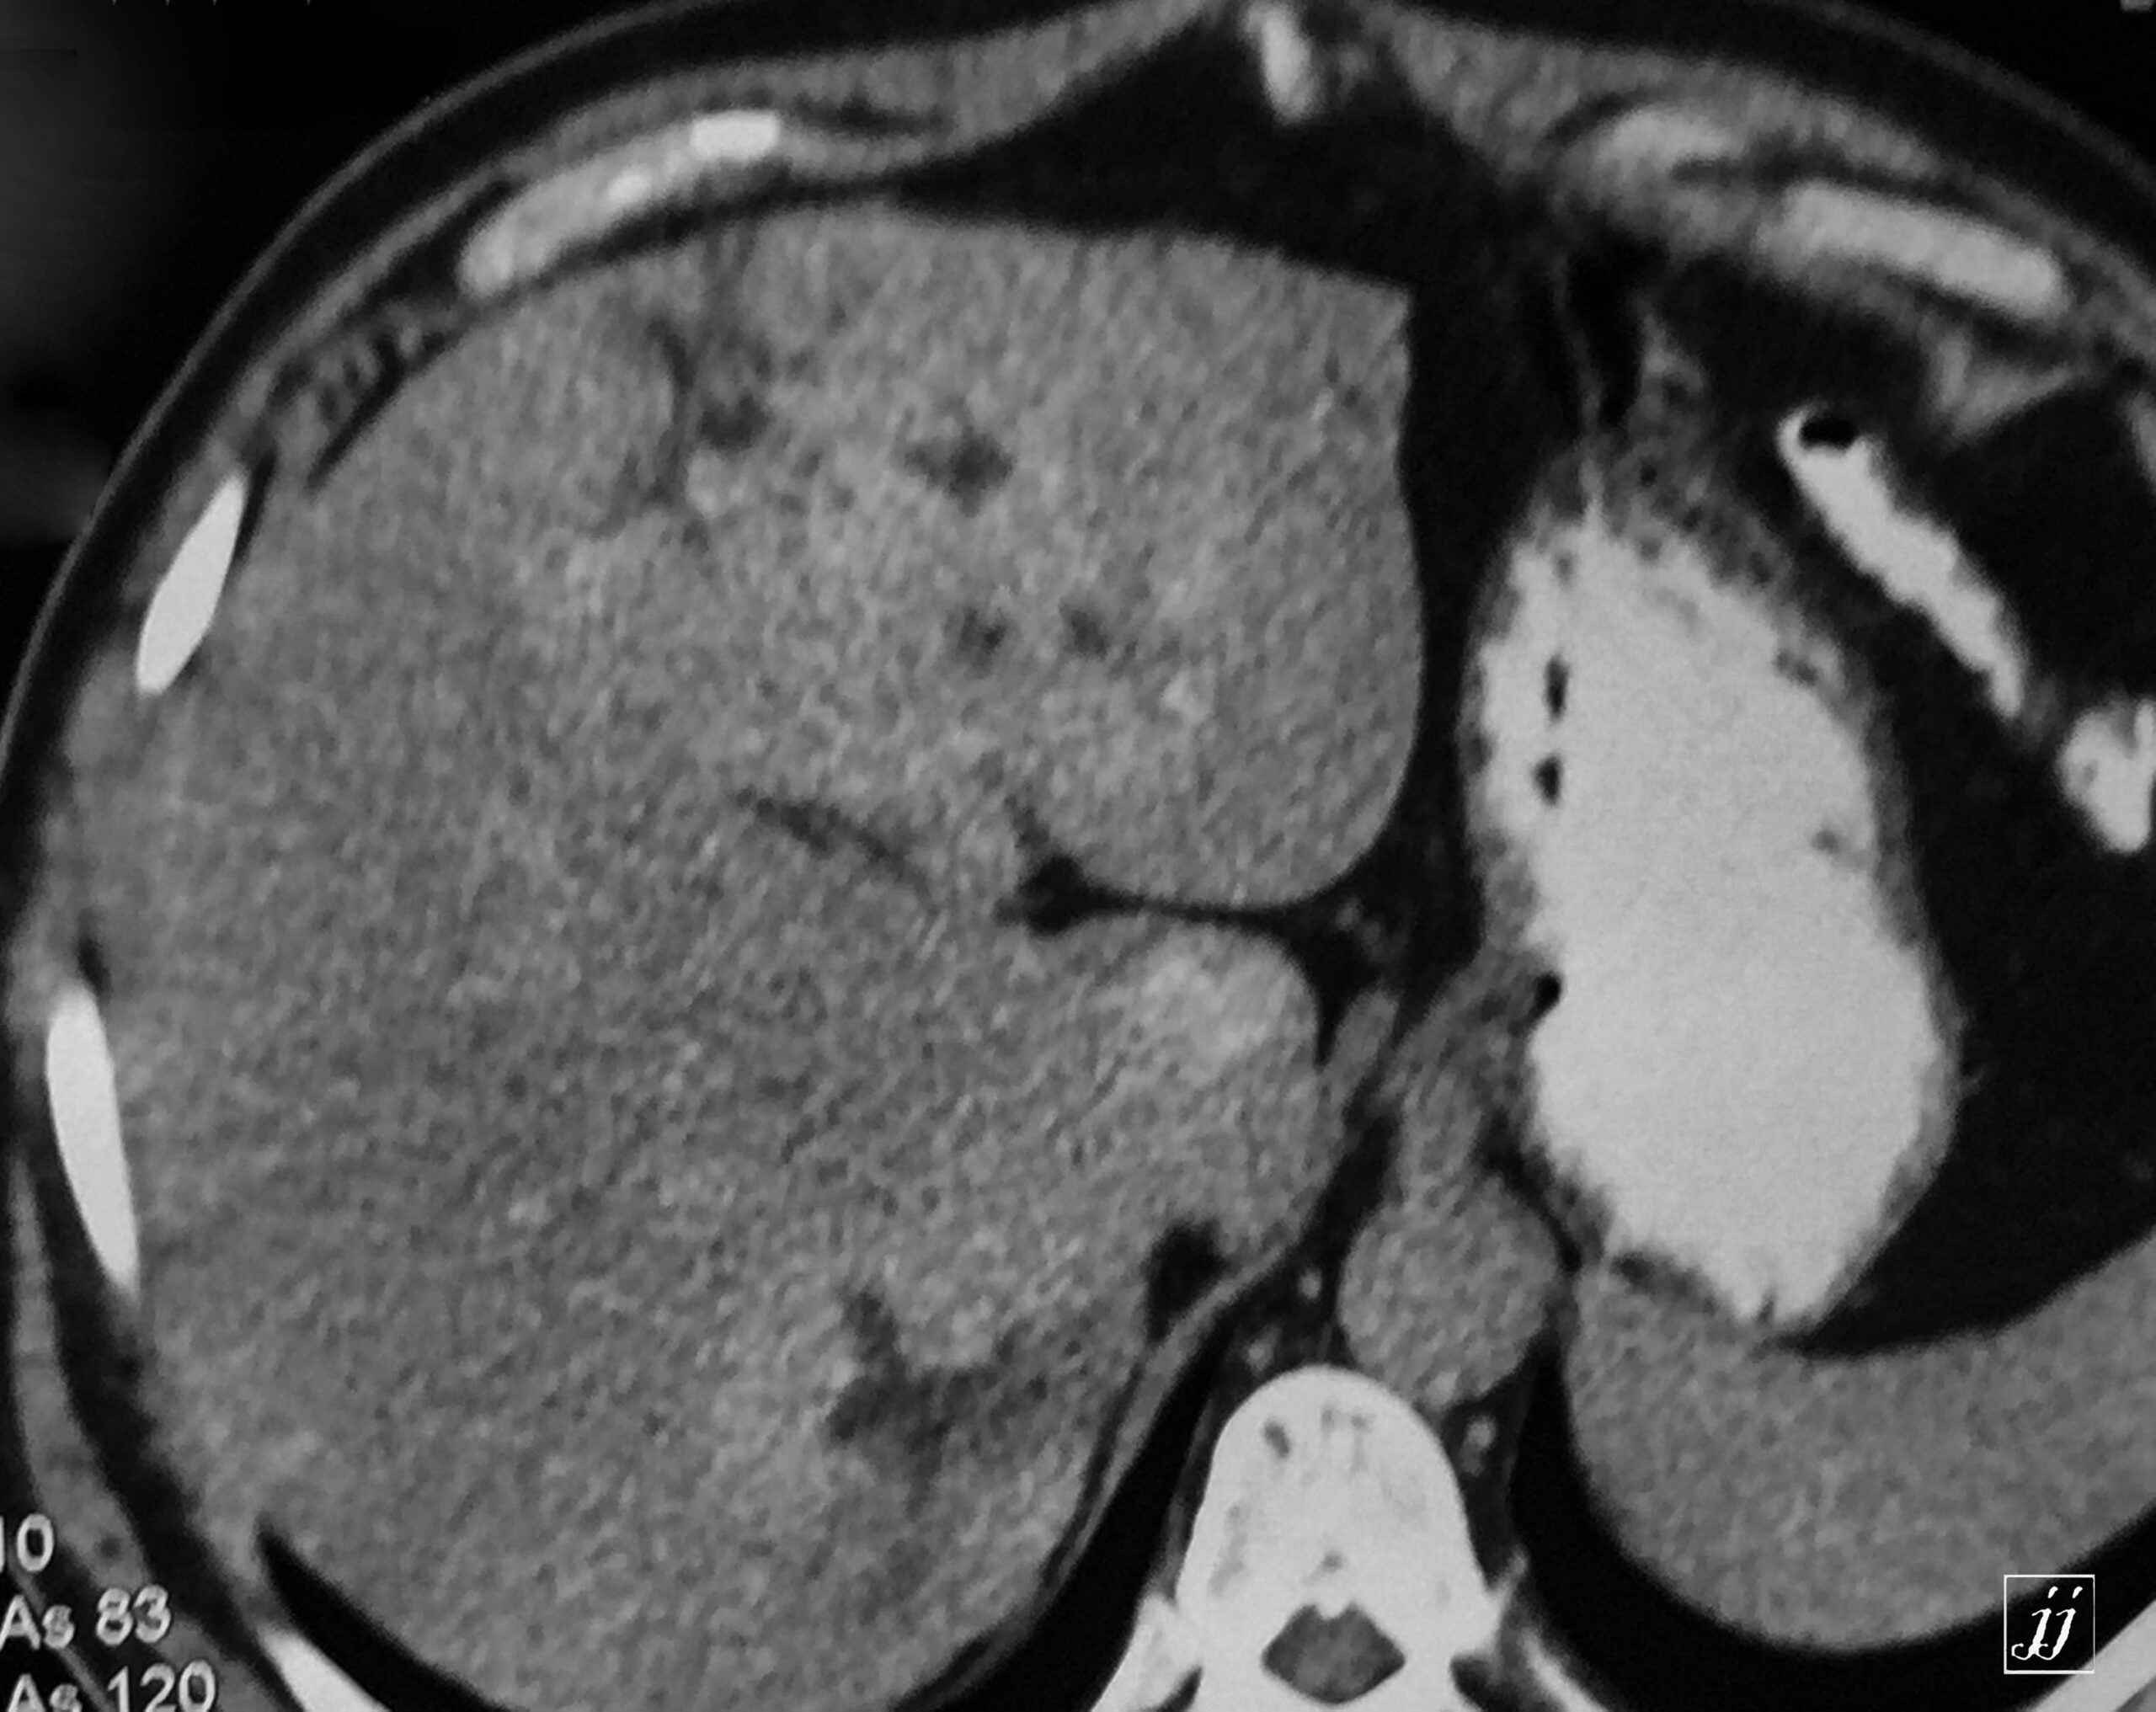

Abdomen- huge exophytic liver hemangioma with another two small hemangiomas (10)